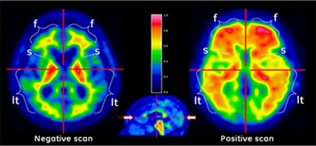

방사성의약품, 잇따른 세계적 스타 치매 소식에 관심 집중

- 2023-02-24 16:09

- 노영희 기자